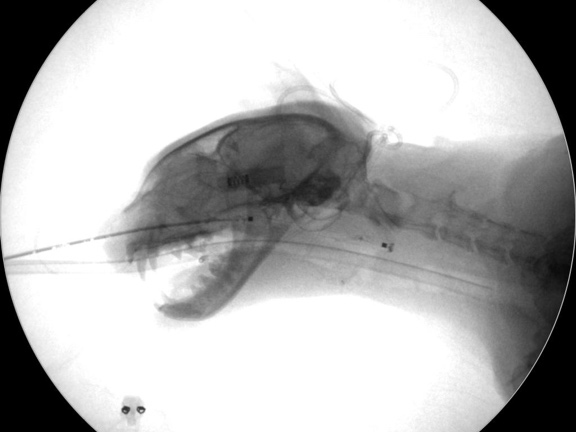

バルーン用のガイドワイヤー

バルーン拡張術の様子

Cアームにて拡張部位の確認